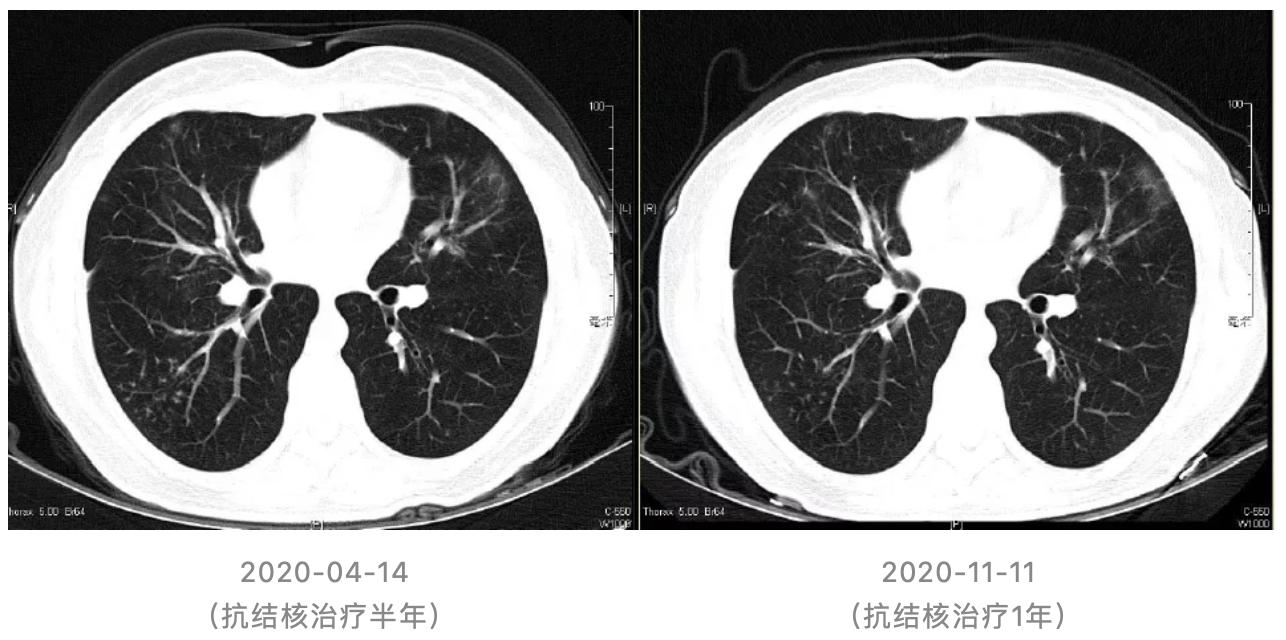

开始予四联抗结核:异烟肼0.3g qd po,利福平0.45g qd po,乙胺丁醇0.75g qd po,吡嗪酰胺0.5g tid po

停用硫唑嘌呤;糖皮质激素逐步减量至停用。

转归:

(1)抗结核治疗1月后随访胸部CT:

(2)抗结核治疗1年随访胸部CT: